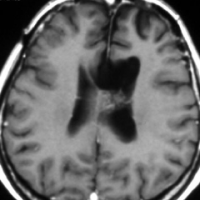

小児期の低線量照射で生じた多発性髄膜腫

5歳の時に白血病,化学療法と低線量頭蓋照射で治りました。ちゃんと就職して重機の運転をしていましたが,30歳,左足の痙攣で発症しました。多発性髄膜腫が発生していました。摘出する必要があるものです。グレード1の良性の髄膜腫です。